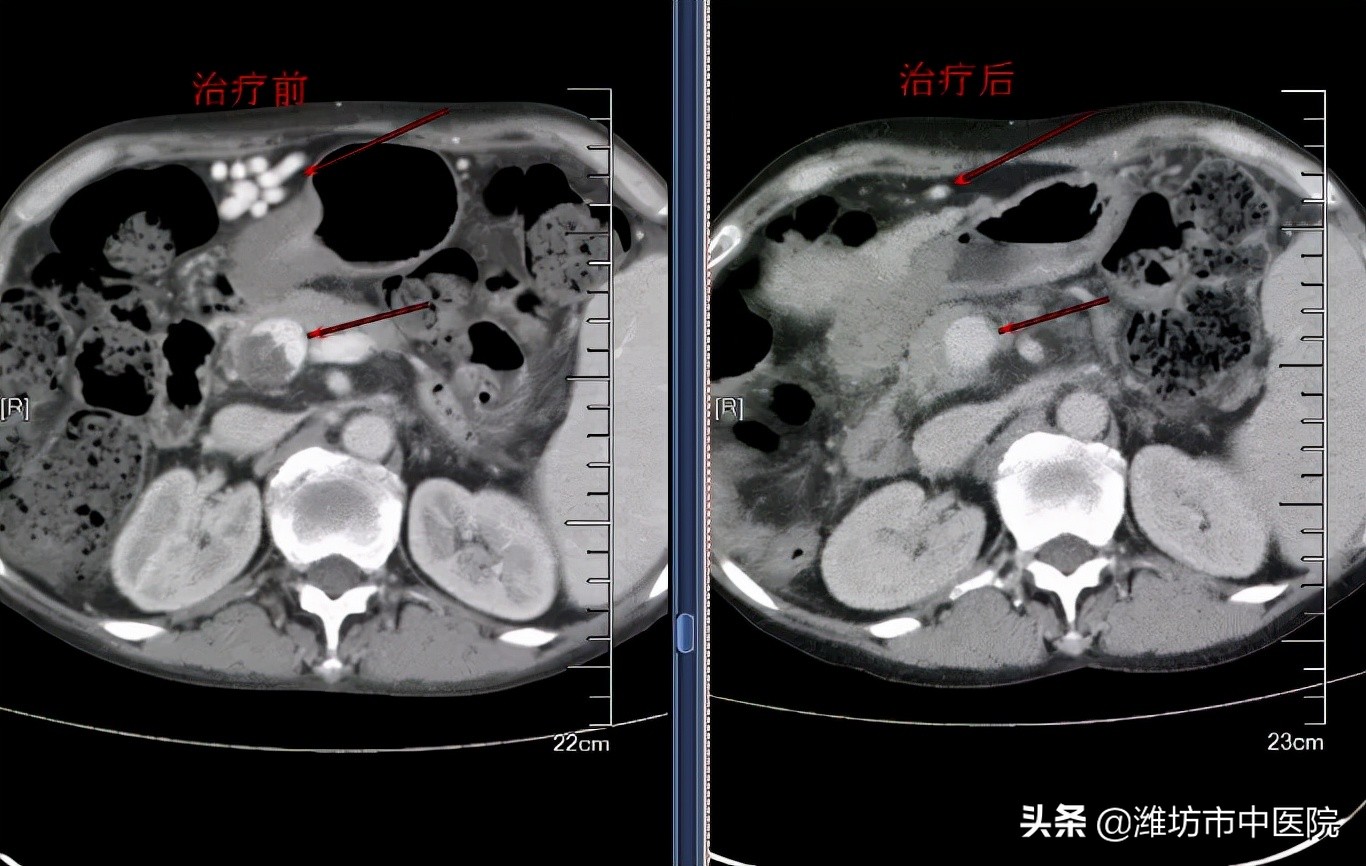

姜女士的情况是消瘦乏力、精神不振、懒言且语声无力,纳差、不欲饮食,稍多食即有饱胀感,舌质红嫩、边有齿痕、少苔,脉短而涩。中医辨证确为“虚劳”,证属“气血亏虚”,于是给予八珍汤加减。服药5剂后,姜女士即自觉体力恢复、精神饮食皆有好转,查房时对医护人员表示,“中药口感好,喝后很舒服”,主动要求再喝中药。肝胆内科团队综合考虑认为,目前方证相符、辨证准确,继而制定长期中医治疗方案,给予中药汤剂调节治疗。服药2个月后复查后传来喜讯,门静脉栓子消失、腹壁下曲张静脉丛明显减轻、腹水消失,肝功能*级A**。肝癌治疗的障碍被扫除,姜女士顺利进行了后续疗程,身体状况日渐恢复。